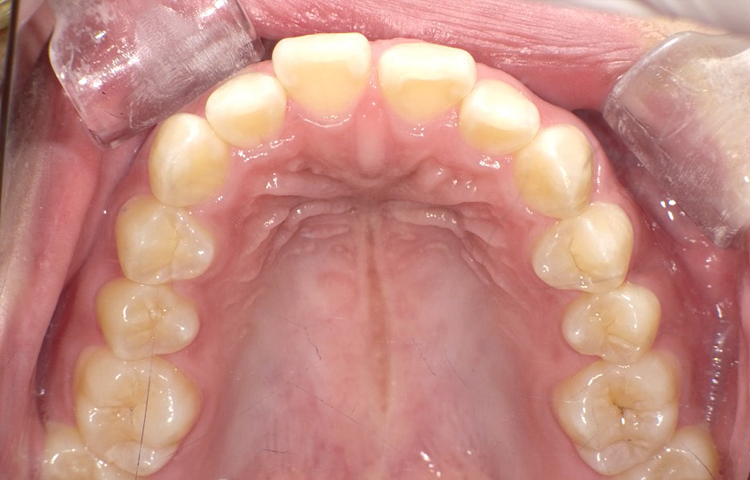

症例3

治療前

治療後

| 主訴 | 上下前歯全体の歯並びが気になる |

|---|---|

| 治療 期間 |

約6ヶ月 |

| 治療費 | 330,000円(税込)/調整費用別途 |

| 治療 内容 |

上下の前歯部にワイヤーを着けて進めていく、プチ矯正で施術。 |

| 治療の リスク |

固定の装置をつけないと後戻りしてしまう。 |